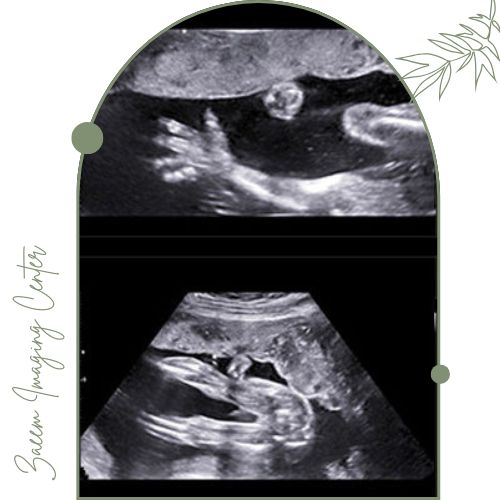

سونوگرافی آنومالی جنین

سونوگرافی آنومالی جنین یکی از مهمترین مراحل غربالگری دوران بارداری است که معمولاً در هفتههای ۱۸ تا ۲۲ بارداری انجام میشود. هدف اصلی این روش بررسی دقیق وضعیت و ساختار ارگانهای حیاتی جنین شامل مغز، ستون فقرات، قلب، کلیهها، دستگاه گوارش و اندامهاست تا ناهنجاریهای مادرزادی و نقائص احتمالی از جمله ناهنجاریهای ساختاری، مشکلات رشد یا اختلالات کروموزومی به موقع شناسایی شوند. با استفاده از دستگاههای سونوگرافی پیشرفته و تیم متخصص تصاویر واضح و تخصصی تهیه شده و هرگونه مشکل احتمالی به پزشک گزارش میشود تا تصمیمگیری دقیق در ادامه روند بارداری و برنامهریزی درمانی صورت گیرد. این سونوگرافی معمولاً بدون درد است و نقش بسیار مهمی در حفظ سلامت مادر و جنین ایفا میکند.